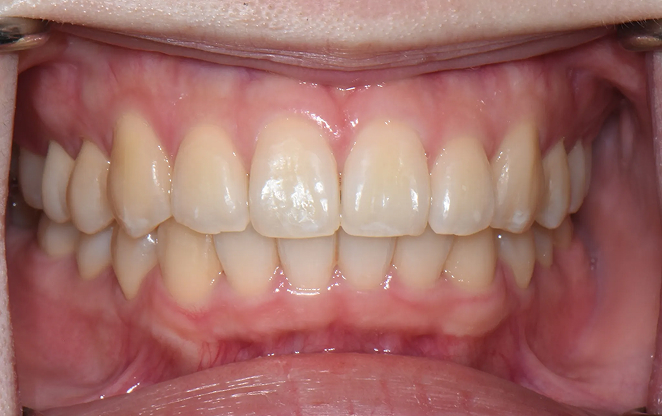

비보철 교정은 치아를 뽑거나 보철물을 사용하지 않고,

내 치아 그대로의 아름다움을 지켜가며 교정하는 방법입니다.

불필요한 보철 없이 치아의 배열을 조정해, 자연스럽고 건강한 치아와

균형 잡힌 미소를 찾아가는 과정입니다. 자연스러움 속에서 완성되는

건강한 미소, 비보철 교정으로 그 여정을 시작하세요.